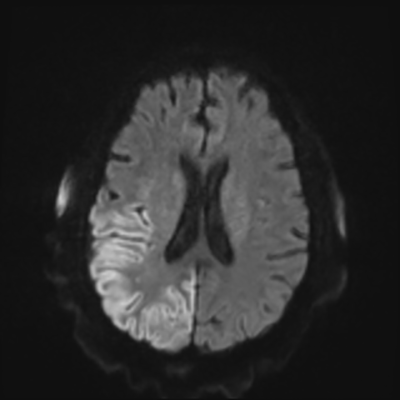

You come back the next day and see how things are going. The patient's electrographic record has shown a moderate encephalopathy (diffuse slowing, disorganization) with frequent right posterior quadrant delta slowing. Based on this result, and an adequately improved clinical examination, you give the okay to proceed with obtaining an MRI of his brain. This is shown below.

MRI brain (DWI)